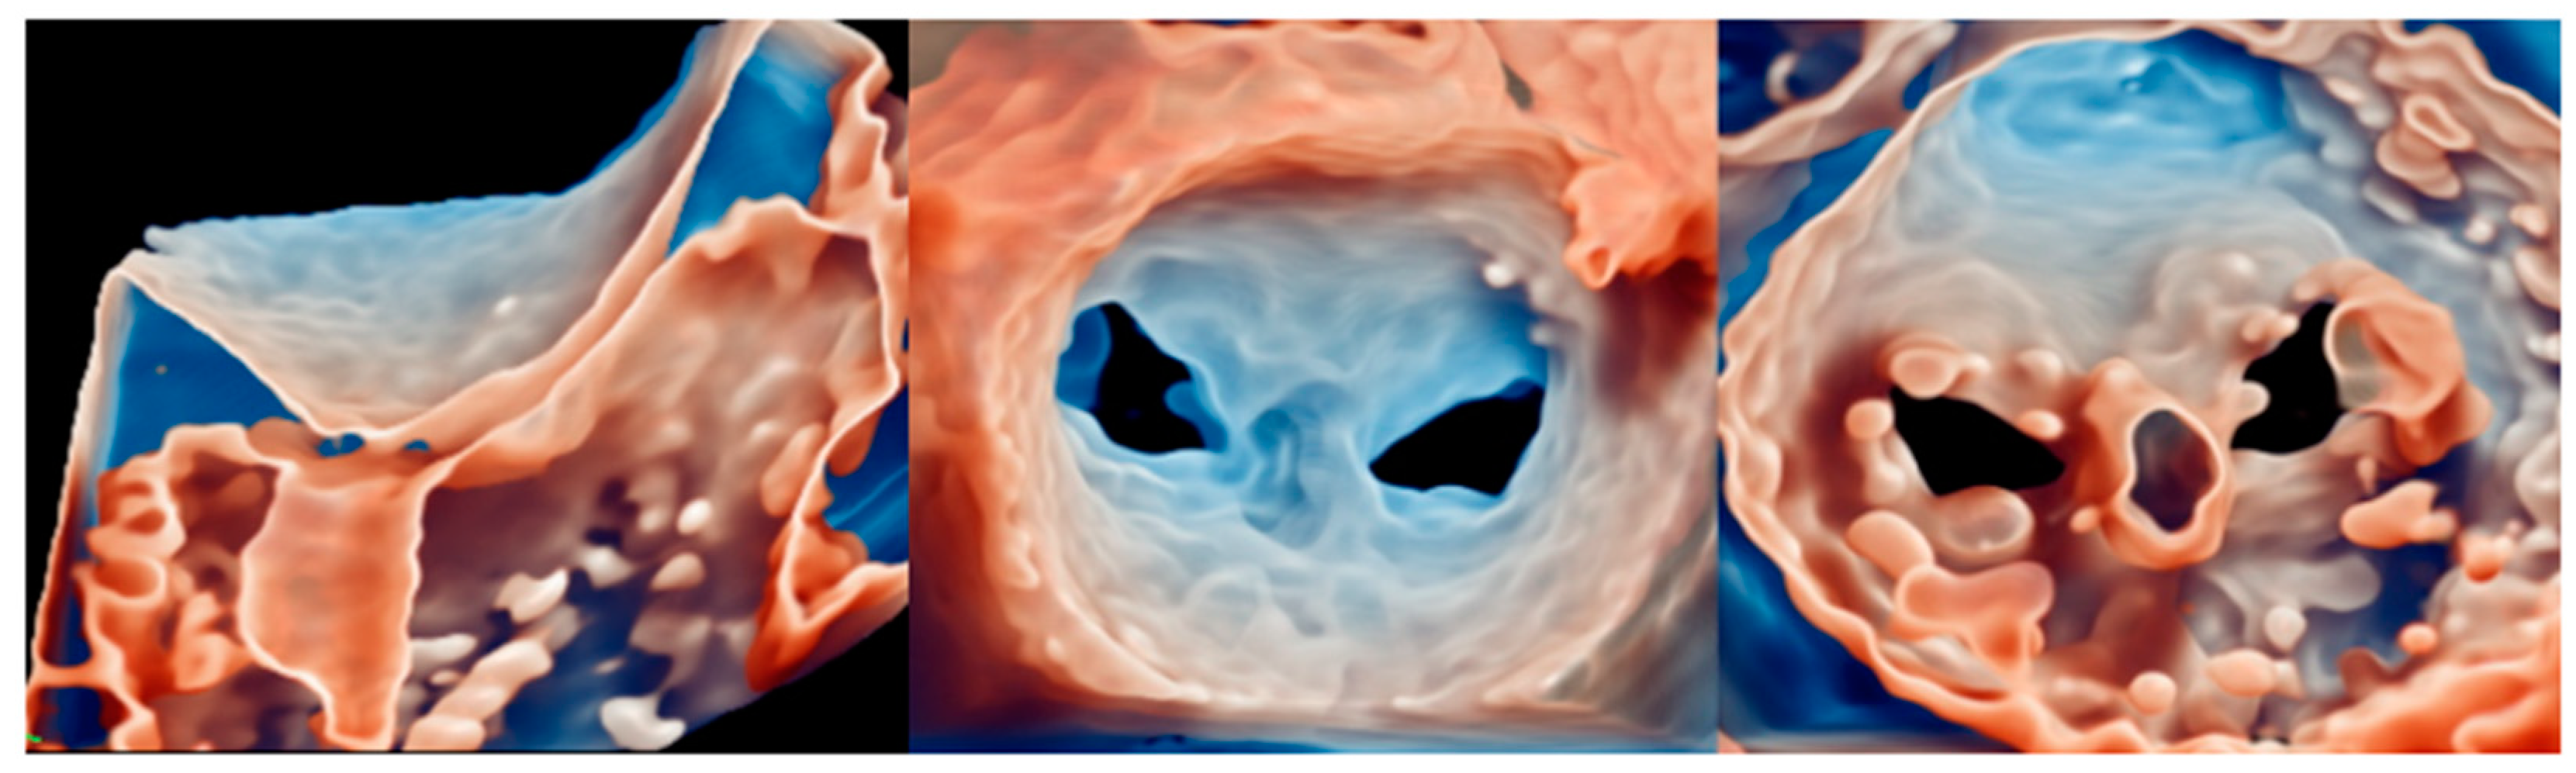

4.4. TMVR

5.5. TMVR

6.4. TMVR